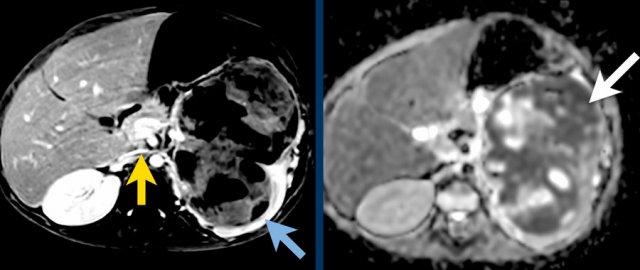

Đây là hình ảnh T1W axial có tiêm gadolinium với kỹ thuật xóa mỡ.

Hình ảnh cho thấy sự bao bọc của các mạch máu.

Lưu ý sự lan rộng của khối u ra phía sau động mạch chủ, đẩy động mạch chủ ra xa cột sống (mũi tên).

Mức độ lan rộng của khối u được đánh giá rõ ràng trên chuỗi xung TSE T2 weighted 3D theo mặt phẳng axial.

The left kidney is compressed and displaced caudally.

Có di căn hạch bạch huyết cạnh động mạch chủ (mũi tên vàng nhỏ).

Nguyên ủy của thân tạng và động mạch mạc treo tràng trên bị khối u bao quanh (đầu mũi tên).

Tĩnh mạch chủ dưới bị đẩy ra phía trước (mũi tên xanh).